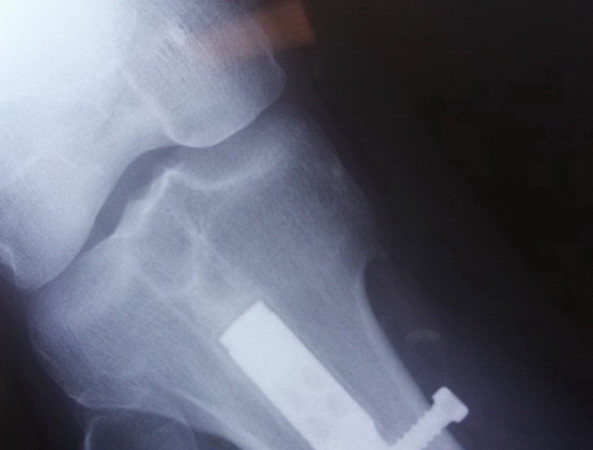

Le realizamos estudio Rx no hallando daño aparente en el mismo. Se puede ver parte del clavo de titanio que le implantamos en la tibia a principio de la temporada 2008.